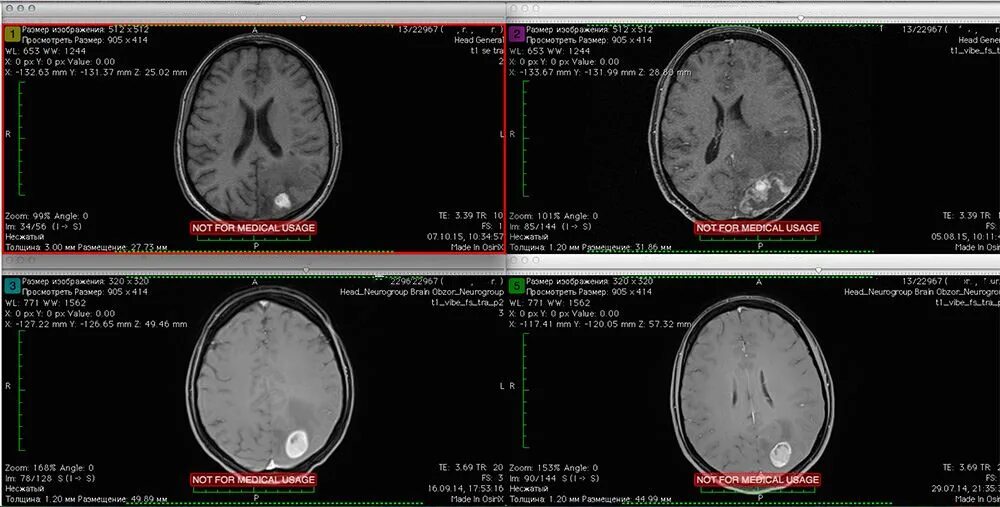

Лучевая терапия метастазов в лимфоузлах